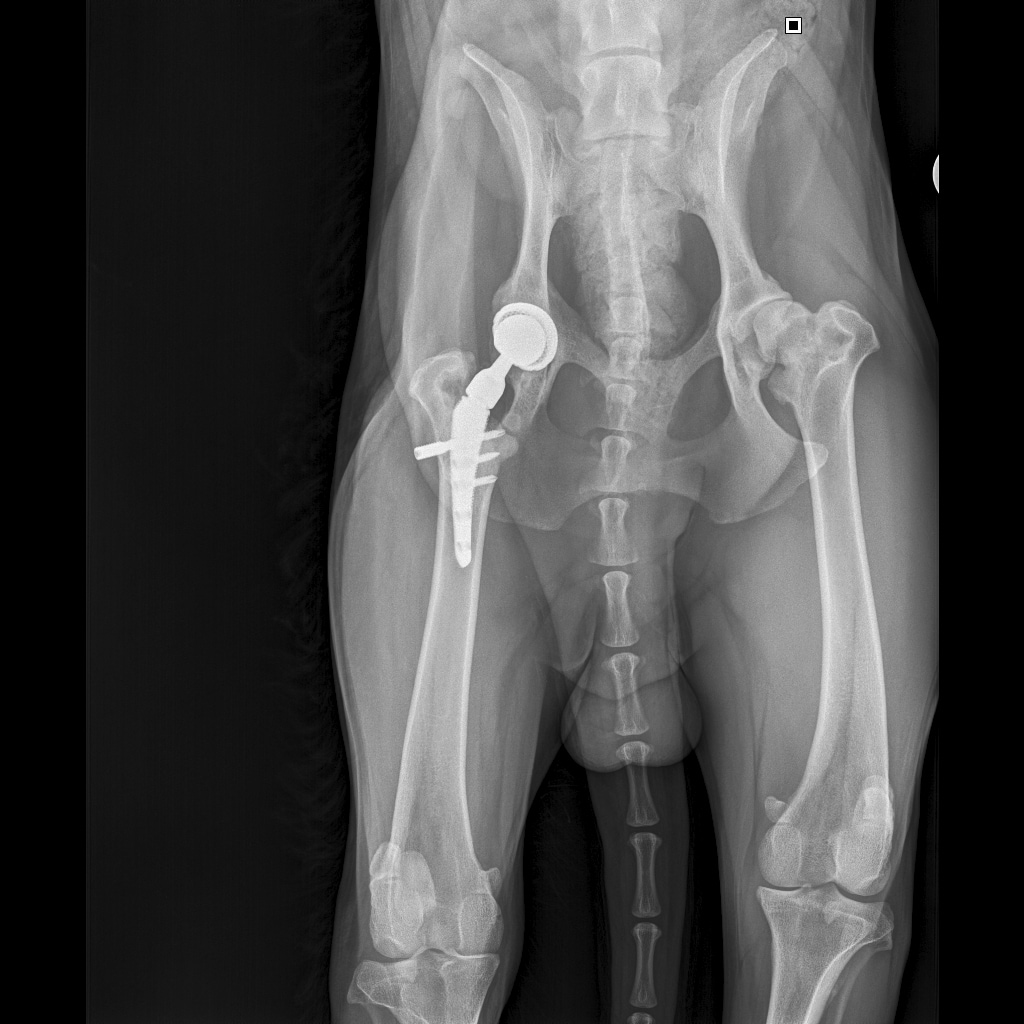

E358D56E-67BF-4D4C-B3F0-BF8F4089D7A2.jpeg

767DD36C-E2E2-41FB-9CCF-6940421D2BB2.jpeg

701487DA-D6D9-4CE0-B18B-EEB120E78EF2.jpeg

Мы ничего не оплачивали. Все включено.

За время противовоспалительной терапии снизилось воспаление и в левом тазобедренном суставе, но увы, форма головки бедренной кости и состояние шейки бедра , лучше не стали:(((

Операция однозначно нужна.

Снимки столь качественные, что их можно в учебник